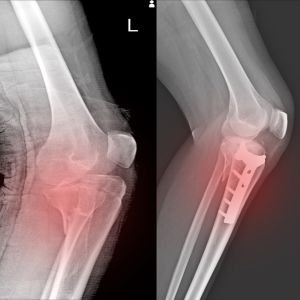

Bone & Joint X-Ray

Used to identify fractures, arthritis, and joint issues, bone and joint X-rays help in diagnosing musculoskeletal conditions quickly and accurately.